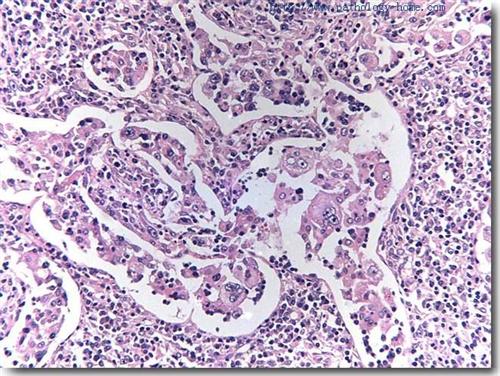

伴有巨大淋巴结病的窦性组织细胞增生症(shml)

窦性组织细胞增生伴巨大淋巴结病

图片尺寸500x376